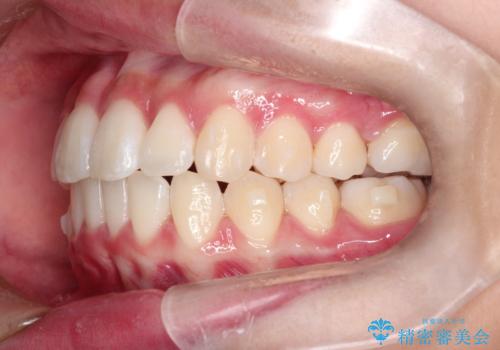

前歯のがたがたを綺麗にしたい

- 前歯がねじれていること、出ていることを主訴に来院されました。

前歯の突出感も改善され、満足していただきました。